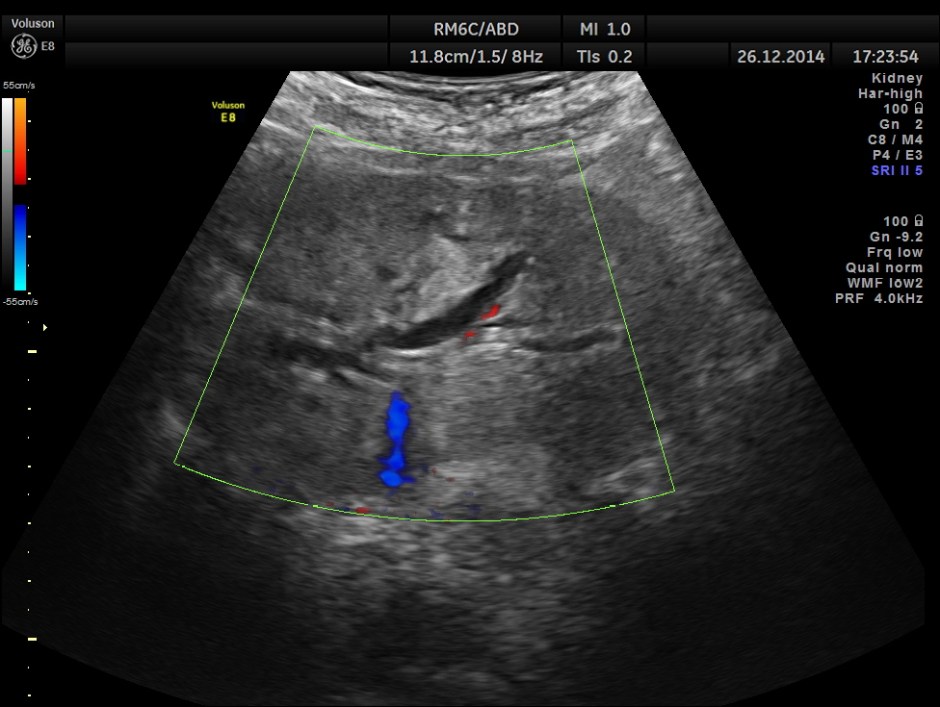

dilated pancreatic duct is seen

the head region of the pancreas shows an irregular mass lesion

This was a case of Carcinoma of the head of the pancreas , causing biliary obstruction and also pancreatic ductal obstruction , with possible peritoneal deposits.